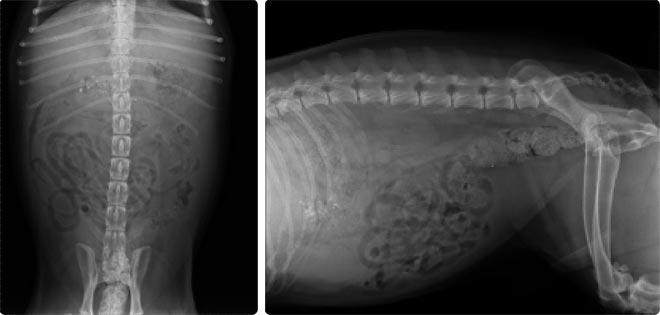

- Perfil bioquímico: níveis elevados de enzimas hepáticas podem ser observados e a presença de bile na urina. Radiografias e ecografias.

- Radiografias e ecografias: permitirão visualizar o fígado e possíveis vazamentos de bile.